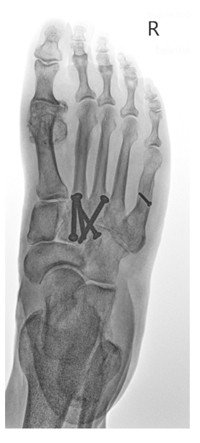

Ein halbes Jahr nach dem ersten Schmerzereignis stellte sie sich in unserer Sprechstunde vor. Es zeigten sich ein hinkendes Gangbild sowie ein ausgeprägter Druckschmerz im Bereich des zweiten Mittelfussknochens. Eine wesentliche Schwellung war nicht nachweisbar. Röntgenologisch konnte eine Pseudarthrose, das heisst ein Ausbleiben der Knochenbruchheilung, festgestellt werden.

Auch wir empfahlen der Patientin das konsequente Tragen der Carbonfasereinlage und boten ihr zusätzlich die Durchführung einer hochenergetischen fokussierten extrakorporalen Stosswellentherapie (ESWT) an. Schon nach der ersten Behandlung kam es zu einer deutlichen Besserung der Schmerzsymptomatik und im Röntgenbild konnten erste Zeichen einer Knochenbruchheilung nachgewiesen werden. Wir entschieden uns für die Durchführung einer zweiten ESWT. Als sich die Patientin sechs Wochen später zur klinisch-radiologischen Kontrolle wieder in unserer Sprechstunde vorstellte, war sie vollständig beschwerdefrei. Röntgenologisch zeigte sich eine vollständige Durchbauung des Bruches (siehe Abb. 2).